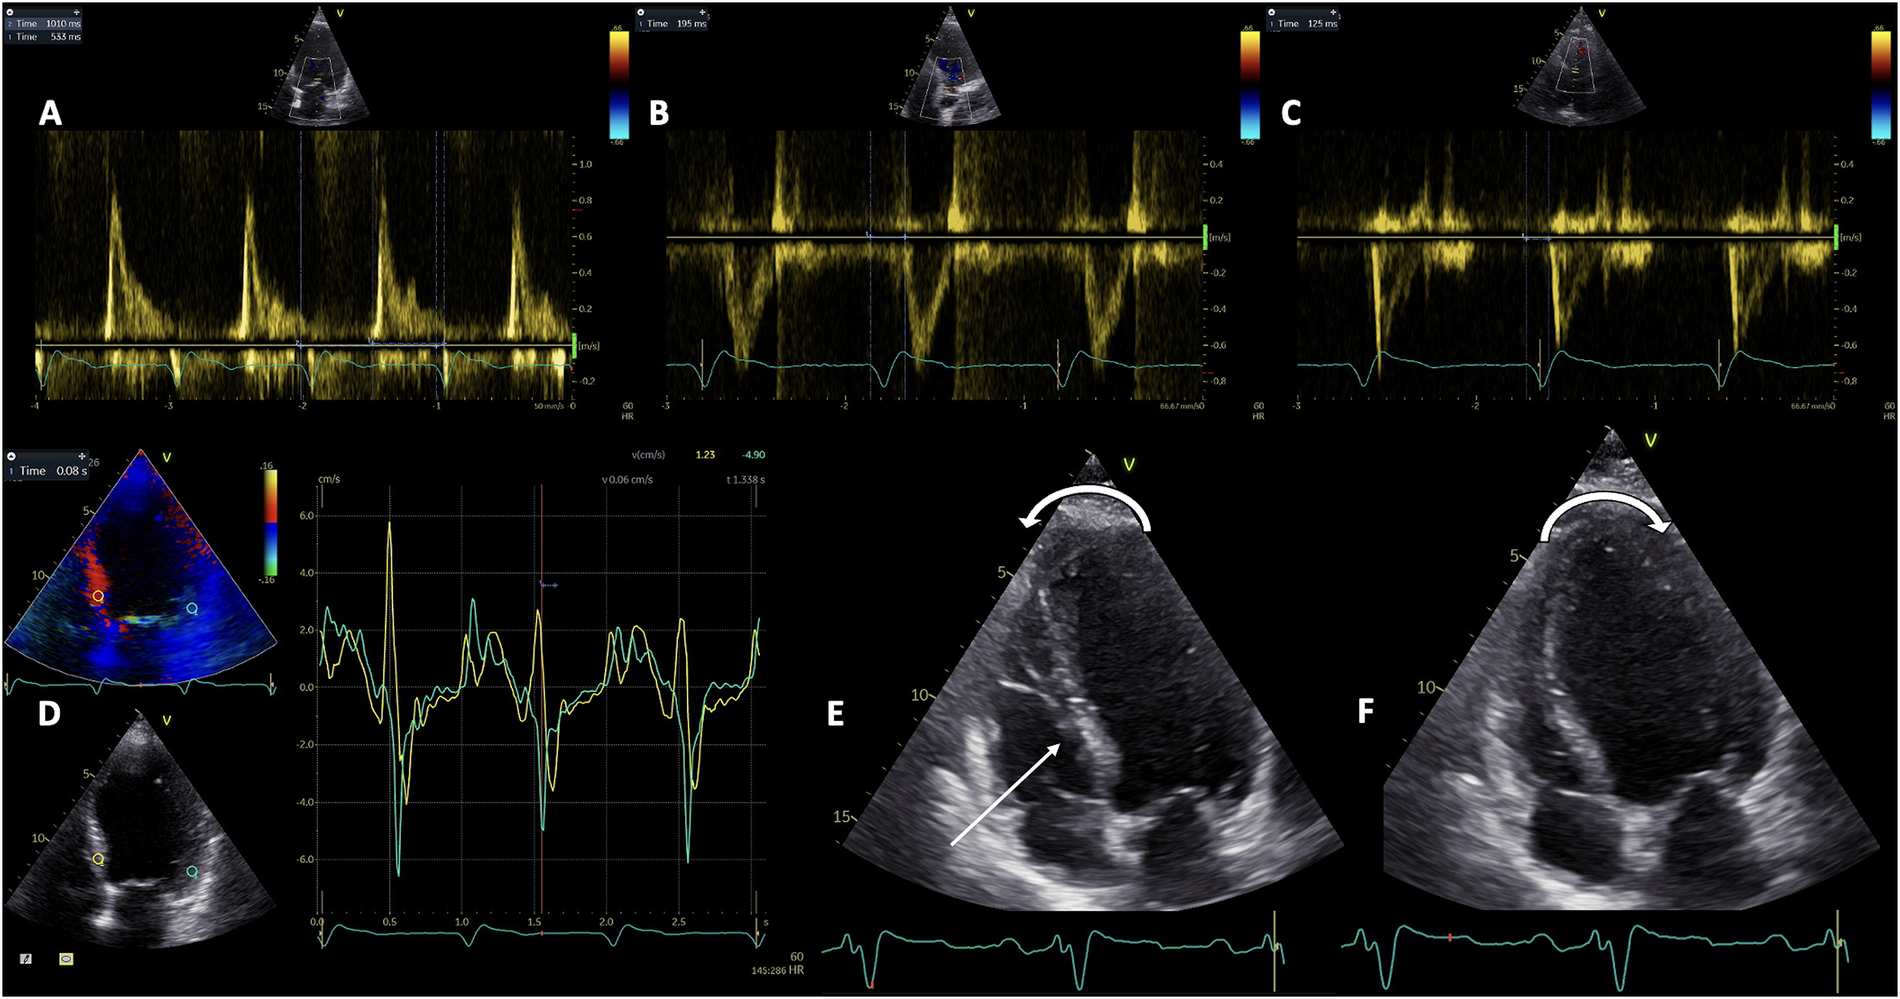

Pulsed-wave (PW) Doppler echocardiography is used for the assessment of all atrioventricular, inter- and intra-ventricular dyssynchronies. Atrioventricular (AV) dyssynchrony is objectivated by a reduced diastolic ventricular filling time, measured by PW Doppler at the level of the mitral valve leaflets’ tips between the onset of the E wave and the end of the A wave, and normalized as a percentage of the cardiac cycle (Figure 1A). A LV filling time <40% indicated significant AV dyssynchrony (42). It can be used only in sinus rhythm and results either from an abnormal delay between the end of atrial systole and onset of ventricular systole in case of a long PR interval, or from a prolonged and abnormal intraventricular conduction (43). Parsai et al. hypothesized that the identification of all types of dyssynchrony would better determine the CRT responders, and conducted a study on 161 patients investigated before and after CRT. They propose an algorithm that includes the identification of 4 subgroups of mechanisms: the presence of true dyssynchrony as SF, impaired diastolic filling with either short or long AV delay, and exaggerated LV-RV interaction. The CRT clinical response depended on correcting the underlying mechanisms involved in the development of HF, and solely relying on the assessment of LV dyssynchrony failed to identify 40% of responders (44).

Figure 1

The evaluation of the three types of mechanical dyssynchrony by Doppler echocardiography. Pulsed-wave Doppler assessment of atrioventricular dyssynchrony as the diastolic filling time relative to cardiac cycle duration (A); and interventricular dyssynchrony as the difference between LV pre-ejection time (B), and RV pre-ejection time (C) Tissue Doppler Imaging evaluation of intraventricular dyssynchrony as the basal septal to lateral wall delay (D) Representation of septal flash and apical rocking (E and F). LV, left ventricle; RV, right ventricle.

Empirically, the interventricular dyssynchrony was considered the interventricular mechanical delay (IVMD), calculated as a difference between LV pre-ejection interval (Figure 1B), and RV pre-ejection interval (Figure 1C) of more than 40 ms. LV and RV pre-ejection intervals are measured by PW Doppler, from the onset of the QRS complex and, respectively, the initiation of aortic and pulmonary ejection flows (45). Several studies confirmed the association between the IVMD and a favorable response to CRT. In the SCART Study Achilli et al. found that an IVMD >44 ms independently predicted the response (46), while patients with IVMD >49 ms benefited significantly from CRT in an analysis by Richardson et al. of the CARE-HF trial (47). However, the IVMD is considered to lack sufficient accuracy to be used for CRT reponse in clinical practice according to the PROSPECT study (6). More recently, as part of the CAVIAR response score developed by the investigators of the MARC study, the vectorcardiographic QRS area, IVMD and ApRock were strongly associated to LV reverse remodeling after CRT (48). The MARC study, which is the only prospective multi-modality biomarker study on CRT response, provided significant insights into the effectiveness of various echocardiographic criteria used, underscoring the importance of combining different parameters to improve the accuracy of CRT response prediction.

Tissue Doppler Imaging (TDI) is essential for the accurate determination of the amplitude, timing of onset, and peak systolic and diastolic velocities in correlation with the ECG signal. PW TDI is useful for measuring the electromechanical delay (58, 59), and the electro-systolic delay (60), from the beginning of the QRS interval to S wave onset, and to peak systolic contraction, respectively. Additionally, color TDI loops can be recorded and subsequently analyzed offline as reconstructed signals, in order to overcome the well-known limitations of PW TDI. The color-coded TDI has been the method of choice for assessing dyssynchrony by echocardiography for many years (61). The dyssynchrony indices obtained by color TDI are basal septal to lateral wall delay (Figure 1D), maximum time to peak systolic velocity in the slowest of 6 basal LV segments, as well as the Yu index which integrates data from the 3 apical LV views and represents a 12-segment model (62). While Bax et al. elegantly demonstrated that the degree of LV dyssynchrony predicted the clinical response and LV remodeling after CRT, with a cut-off value of 65 ms for the opposite wall delay (63), a Yu index or mechanical dyssynchrony index ≥33 ms managed to predict LV remodeling in patients with a QRS duration >150 ms with a sensitivity of 100% and specificity of 78% (64). An alternative approach to the Yu index is calculating the time to peak systolic velocity in all the segments, for which a value ≥100 ms is predictive of the CRT response (61). However, the 12-segment model has higher variability and the disadvantage of being more technically challenging (65).

5.2 Visual assessment of apical rocking and septal flash

Both ApRock and SF occur as a consequence of the mechanical dyssynchrony secondary to the LBBB (15), and their superiority over conventional parameters has already been demonstrated in several prospective observational studies (68, 69). ApRock (Figures 1E,F) is characterized as an initial septal contraction in the LV isovolumic contraction period which results in a short inward motion of the septum and causes the apex to move septally. Next, the delay in the activation of the lateral wall pulls the apex laterally during the ejection time while stretching the septum (68, 70). SF is caused by an initial thickening/thinning of the septum during isovolumic systole (Figure 1E). This phenomenon can also be easily identified using M-mode echocardiography in the parasternal long-axis view or tissue Doppler imaging in both the short and long parasternal long-axis views (71), while a low-dose dobutamine administration may help unmasking the SF in a minority of challenging cases (72).